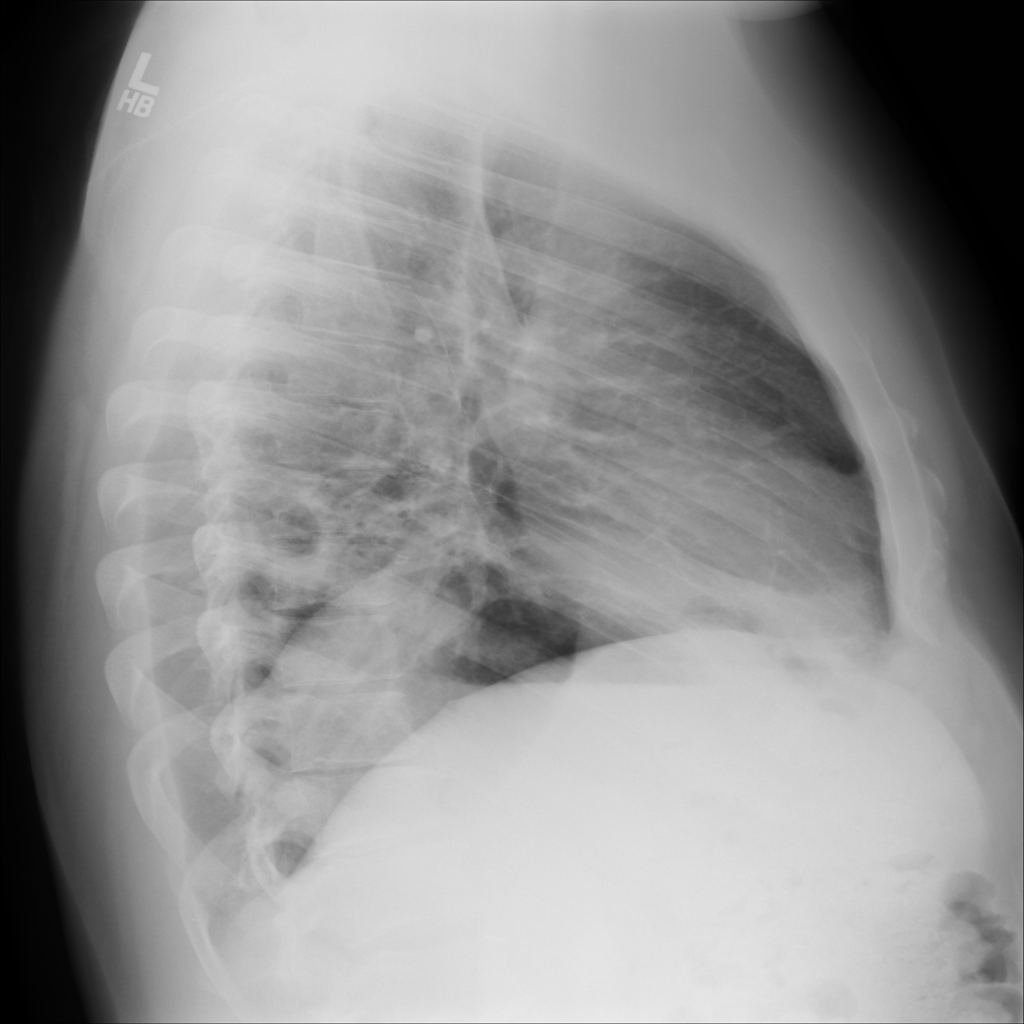

PAT-E960 · IMG-002Fibrosis

PAT-E960 · IMG-002

PA